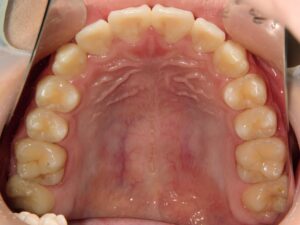

第1期治療開始時

顔貌写真

口腔内写真

年齢

9歳 男性

主訴(患者様のお悩み)

歯のデコボコを治したい

診断

上顎前歯部叢生(上の前歯のデコボコ)

上下顎側切歯クロスバイト(部分受け口)

上顎狭窄歯列(上のあごが小さめ)

歯冠幅径大(歯が大きめ)

治療方針

上顎緩徐拡大(上あごを拡大)

上の前歯部のみワイヤー矯正

使用装置

緩徐拡大装置(クワドヘリックス)

前歯部ブラケット

治療期間の目安:約半年~1年(保定期間を除いた期間)